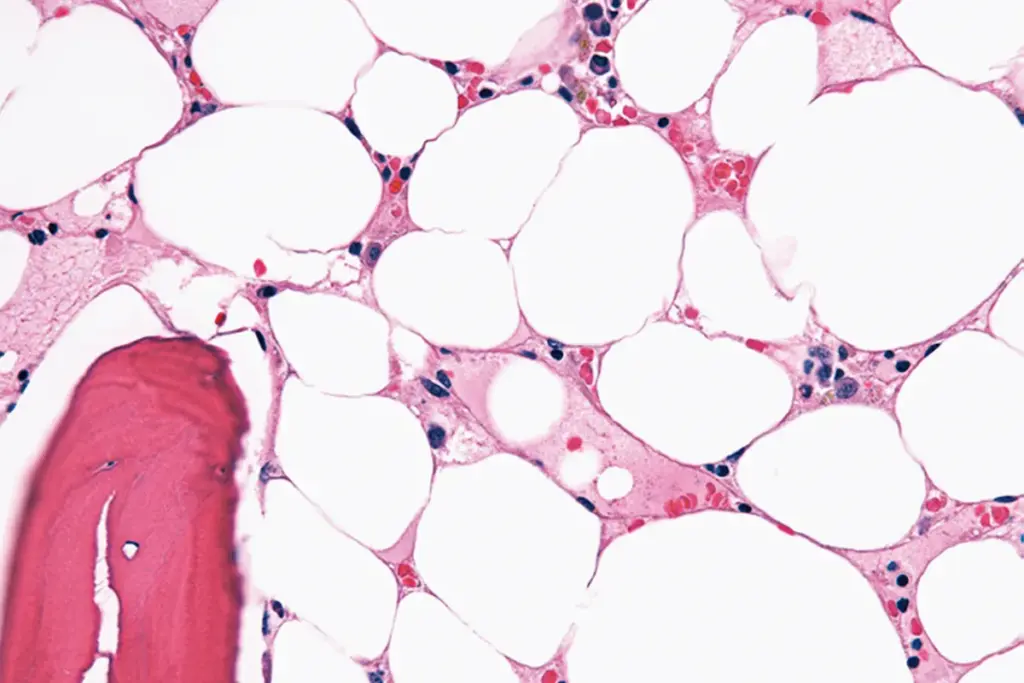

Microscopic Insights: What Stem Cells Look Like

Stem cells are key for bone marrow transplants. They are small and have a big nucleus compared to their cytoplasm. This is important for making new blood cells.

Seeing stem cells under a microscope helps us understand bone marrow transplants better. It shows how these cells are important for the transplant’s success.